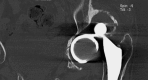

Case report: Painless chronic liner dissociation of a total hip arthroplasty

Background: Dislocation or liner dissociation of a total hip prosthesis usually results in pain and discomfort. Although several reports describe chronic dislocation and its treatment, chronic liner dissociation is an unreported complication.

Case description: We report an unrecognized dissociation and displacement of the liner of a total hip prosthesis after revision THA. The patient had virtually no pain or functional restrictions. The patient's only complaint was pain on the contralateral side, associated with a leg-length discrepancy. Since the patient had no complaints relative to the liner dissociation we elected not to pursue further treatment. The contralateral pain was treated successfully with a shoe lift.